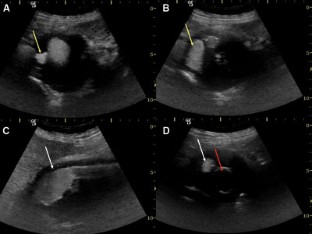

Fig. 5. A–D.